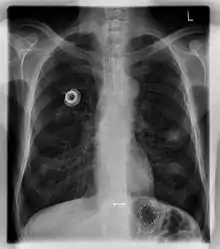

The port is usually inserted in the upper chest (known as a "chest port"), just below the clavicle or collar bone, with the catheter inserted into the jugular vein.

A port consists of a reservoir compartment (the portal) that has a silicone bubble for needle insertion (the septum), with an attached plastic tube (the catheter). The device is surgically inserted under the skin in the upper chest or in the arm and appears as a bump under the skin. It requires no special maintenance other than occasional flushing to keep clear. It is completely internal so swimming and bathing are not a problem. The catheter runs from the portal and is surgically inserted into a vein (usually the jugular vein or less optimally the subclavian vein). Ideally, the catheter terminates in the superior vena cava or the right atrium. This position allows infused agents to be spread throughout the body quickly and efficiently.

The port is then sutured on two sites to the underlying muscles. The tip of the catheter is checked for kinks and position using a fluoroscope. Besides that, aspiration of blood and contrast injection through the chemoport can also be used to confirm the position. The port is the closed in two layers (subcutaneous tissue is sutured first, followed by the skin). Sterile dressing is then placed on the port.[3] The optimum site to park the tip of the catheter is at the cavo-atrial junction or with margin of error of not more than 4 cm above the junction.[3]

Ports can be put in the upper chest or arm. The exact positioning itself is variable as it can be inserted to avoid visibility when wearing low cut shirts, and to avoid excess contact due to a backpack or bra strap. The most common placement is on the upper right portion of the chest, with the catheter itself looping through the right jugular vein, and down towards the patient's heart.